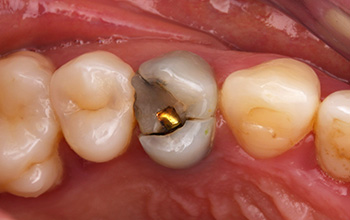

Une patient de 41 ans, consulte au cabinet pour une gêne esthétique et une douleur à la mastication en regard de 14.

Fig. 01 : situation clinique initiale vue vestibulaire, vue latérale et vue occlusale mettant en évidence la fracture du pan palatin de la 14.